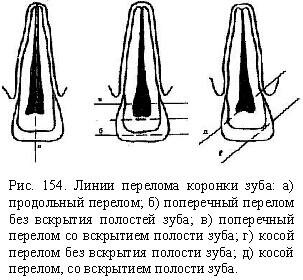

Перелом зуба может произойти на разных уровнях коронки или корня с вскрытием или без вскрытия пульпы. В зависимости от направления линии перелома различают поперечные,, продольные и косые переломы.

Перелом зуба может произойти на разных уровнях коронки или корня с вскрытием или без вскрытия пульпы. В зависимости от направления линии перелома различают поперечные,, продольные и косые переломы.

Переломы зубов бывают в области коронки, корня, коронки и корня, выделяют микропереломы цемента, когда участки цемента с прикрепленными прободающими (шарпеевыми) волокнами отслаиваются от дентина корня. Наиболее часто встречаются переломы коронки зуба в пределах эмали, эмали и дентина со вскрытием пульпы. Линия перелома может быть поперечной, косой и продольной. Если линия перелома поперечная или косая, проходящая ближе к режущей или жевательной поверхности, отломок, как правило, теряется. В этих случаях показано восстановление зуба путем протезирования вкладками, искусственными коронками. При вскрытии пульпы ортопедические мероприятия проводят после соответствующей терапевтической подготовки зуба.